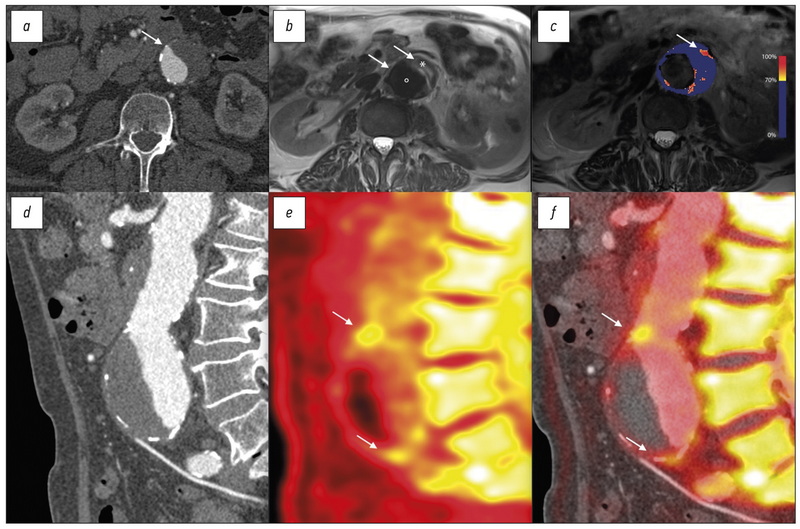

Objective criteria for MRI evaluation of the effectiveness of treatment of bone metastases in patients with prostate cancer and breast cancer: systematic review and meta-analysis

BACKGROUND: The possibility of a personalized approach to the treatment of metastatic prostate cancer and breast cancer requires objective methods for the evaluation of the response of foci treatment in the skeleton. The proven high efficiency of MRI in detecting bone metastases, in combination with the absence of ionizing radiation, has laid the groundwork for using this method in monitoring the treatment course based on objective criteria for evaluation of the therapeutic outcome.

AIM: To assess the possibilities of quantitative and semi-quantitative parameters of MRI-evaluation of treatment efficacy (radiation, chemotherapy, hormone therapy, and targeted therapy) of bone metastases that were used in prostate and breast cancer clinical trials.

MATERIALS AND METHODS: We searched the databases Embase, PubMed, Cochrane Central Register of Controlled Trials (CENTRAL), eLibrary until April 1, 2021, using the following keywords: magnetic resonance imaging, MRI, DWI, treatment response, prostate or breast cancer, and bone metastasis. We only included studies related to the MRI-evaluation of treatment efficacy of any type of therapeutic intervention (with the exception of surgery) for metastatic skeletal lesions in this review.

RESULTS: We selected and analyzed 11 out of 312 sources found as a result of the search. It allowed us to identify four groups of objective MRI criteria for evaluating the therapeutic effect in metastatic bone lesions in patients with prostate and breast cancer, including the dynamics of sizes, signal intensity on DWI, ADC, and tumor total diffusion volume (tDV). Changes in these quantitative and semi-quantitative indicators, with only one exception, had the same direction, although they differed in numerical values. A random-effects model was used for analysis considering the presence of statistically significant heterogeneity (p <0,1 for χ2 test; I2 >40%),. The change in ADC as a result of treatment averaged +0.35 [+0.12; +0.49] ×10−3 mm2/s, with average values of ADC before treatment ― 0.83 [0.71; 1.03] ×10−3 mm2/s, after treatment ― 1.18 [0.83; 1.49] ×10−3 mm2/s.

CONCLUSION: MRI is an informative technique for the objective evaluation of the response of bone metastases to therapy in patients with prostate cancer and breast cancer based on quantitative and semi-quantitative parameters. It has significant potential as a diagnostic test instrument for monitoring the effectiveness of treatment of metastatic skeletal lesions.